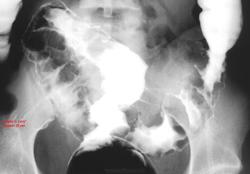

Экспертиза 11. Интересные изображения. Одинаковая патология у 4-х пациентов.

В продолжении темы визуализации "не то, чем кажется", случайная находка в интернете. Предлагаю попробовать угадать патологию. По окончании работы счетчика выложу подсказки, потом ссылку с правильным ответом.

Мы, на наших перифериях не сильно мудрствуем, просто не имеем возможности что либо верифицировать у нас. На мой взгляд, так я бы написал "рак".

Хотя, возможна и лимфома.

Воспалительный псевдотумор.

Местами похоже на инвагинацию.

Наверное, что-нибудь лимфосаркоматозное или лимфопролиферативное с поражением стенки толстой кишки, в последнем случае циркулярным.

Неоднозначно всё